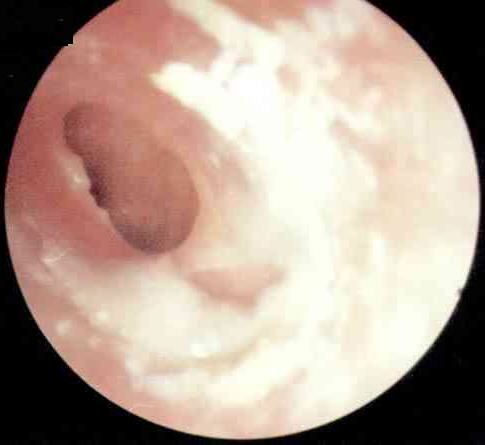

卡他性中耳炎病理图

人们常说人的七窍是相通的。耳朵通过咽鼓管与鼻咽部相通。咽鼓管可以调节耳内的压力,以此与大气压保持平衡,其外还有防御、清洁的功能。在秋冬季,日夜温差比较大,常会诱发上呼吸道感染,炎症波及咽鼓管时,耳内往往会形成负压,这时会产生耳闷的感觉。耳内的黏膜受负压影响分泌较多的液体,并由于咽鼓管功能障碍不能及时排出,积在耳内产生听力下降,耳朵里有水泡声,有时还会感到耳痛。